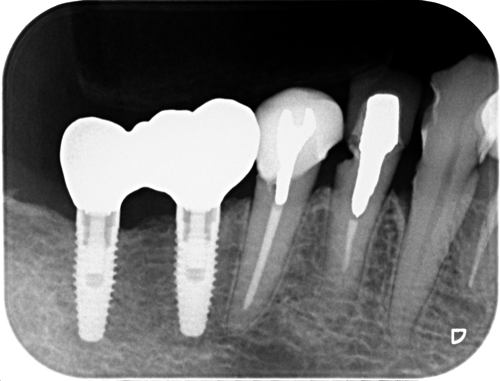

根管治療の必要が無い歯のポストの交換

根尖病変が無くてもむし歯になっていればポストを除去しなければなりません。ポストというのは土台ですね。

下のレントゲンのようなメタルポストは当院ではもう10年以上前から行っていません。レジン系のポストと比べて利点が殆ど無いと思うからです。ただ一つの利点は再治療の際、機材と方法を知っていれば簡単に除去できるということですね。

因みに奥の2本のインプラントは当院で埋入したものでもうすぐ6年経過します。安定しているようです。